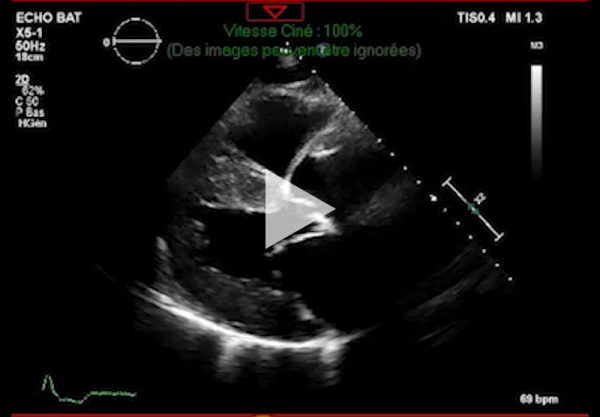

Vidéo 1 - Échocardiographie 2D en incidence parasternale grand axe

- Ventricule gauche non dilaté, hypertrophie concentrique symétrique majeure non-obstructive, hypokinésie globale, aspect scintillant du myocarde

- FEVG 45- 50 %

- Pressions de remplissage VG probablement élevées

- Dilatation bi-atriale marquée (OG 54 ml/m²)

- Fuite mitrale centrale modérée, épaississement des valves

- Ventricule droit non dilaté modérément hypertrophique

- Fonction systolique VD diminuée

- Hypertension pulmonaire peu probable (Vmax IT 2,85 m/s)

- Décollement péricardique minime inférieur